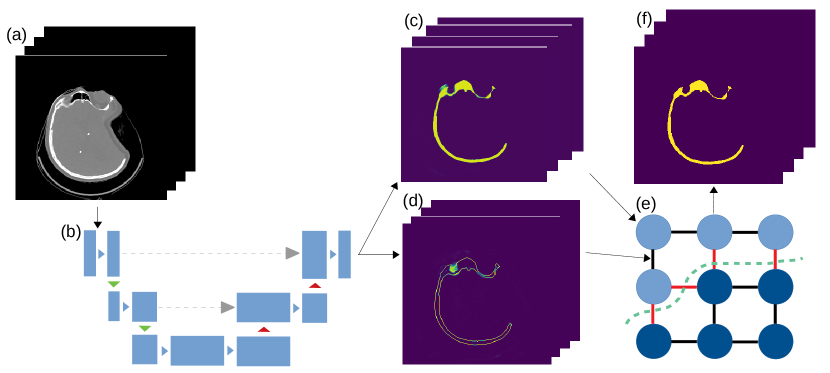

We use the well known U-net model [7] as a baseline method for our segmentation experiments. We experimented with both multi-view (MV) ensemble of 3 orthogonal 2D U-nets as used in [10] and fully 3D U-net [8] since to authors’ best knowledge, the current literature lacks direct comparison between the two approaches. The applied U-net slightly differs from the original architecture by using batch normalization and padding during convolutions, replacing the up-conv layers with bilinear up-sampling and reducing the initial number of convolutions to 16. The architecture of the 3D model is identical except that each convolution, max-pooling, and up-sampling operation is replaced by its 3D equivalent. The networks are trained until convergence using mini batches of shape in case of 2D and in case of 3D model using the Dice loss function [9].

To improve segmentation performance on slightly out-of-distribution data (such as previously unseen medical material or defect shapes), we opted to apply 3D graph-cut segmentation on the CNN output. While this approach has been taken by other authors before [16], we also modify our CNN model to output an edge probability for each voxel in addition to the object probability. Thus, the final layer of the CNN has 3 channels instead of the standard 2. Figure 2 illustrates how this step can provide additional boundary information to the graph-cut in comparison to simply using the conventional intensity or probability gradient. Another advantage of this approach is that since both region and boundary terms have similar dynamic range, finding optimal parameter of the graph-cut algorithm is simplified. We leave throughout our experiments.

Finally, globally optimal 3D segmentation can be obtained by finding minimum cut through this graph [6]. This method will be referred to as CutCNN in the remaining parts of the paper. Note that while the CNN can be either MV (multi-view) or 3D, the graph-cut segmentation is always 3D. The method is summarized in Figure 3.